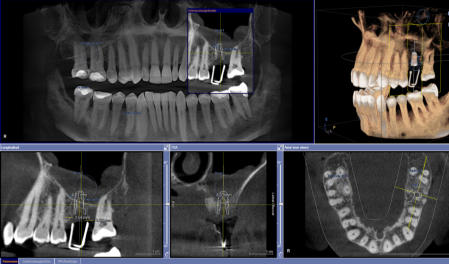

Die 3D-Röntgentechnik oder digitale Volumentomographie liefert 3-dimensionale Ansichten der Kiefer und der Zähne und ist ein großer Gewinn für die zahnärztliche Diagnostik. Bestimmte krankhafte Prozesse werden nur mit diesem Verfahren dargestellt. Häufig werden auch bisher versteckte Befunde entdeckt. Implantatplanungen können mit 3D-Röntgenaufnahmen präziser und vor allem sicherer vorgenommen werden. Exakte Vermessungen sind in diesen Ansichten möglich. Wurzelbehandlung (Endodontie) lassen sich sicher durchführen. Die 3D-Technik ermöglicht ein exaktes Erkennen der Wurzelanatomie, Lokalisieren und Vermessen der Wurzelkanäle. Parodontalbehandlungen (regenerative Parodontologie) lassen sich im Voraus planen. Dadurch kann die Behandlung gezielt und schonend durchgeführt werden. Weitere diagnostische Anwendungsgebiete der digitalen Volumentomographie liegen im Bereich der zahnärztlichen Chirurgie, z.B. für schwierige Weisheitszahnentfernungen, Lagebestimmungen von verlagerten Zähnen und Fremdkörpern.

Die 3D-Röntgentechnik oder digitale Volumentomographie liefert 3- dimensionale Ansichten der Kiefer und der Zähne und ist ein großer Gewinn für die zahnärztliche Diagnostik. Bestimmte krankhafte Prozesse werden nur mit diesem Verfahren dargestellt. Häufig werden auch bisher versteckte Befunde entdeckt. Implantatplanungen können mit 3D-Röntgenaufnahmen präziser und vor allem sicherer vorgenommen werden. Exakte Vermessungen sind in diesen Ansichten möglich. Wurzelbehandlung (Endodontie) lassen sich sicher durchführen. Die 3D- Technik ermöglicht ein exaktes Erkennen der Wurzelanatomie, Lokalisieren und Vermessen der Wurzelkanäle. Parodontalbehandlungen (regenerative Parodontologie) lassen sich im Voraus planen. Dadurch kann die Behandlung gezielt und schonend durchgeführt werden. Weitere diagnostische Anwendungsgebiete der digitalen Volumentomographie liegen im Bereich der zahnärztlichen Chirurgie, z.B. für schwierige Weisheitszahnentfernungen, Lagebestimmungen von verlagerten Zähnen und Fremdkörpern.